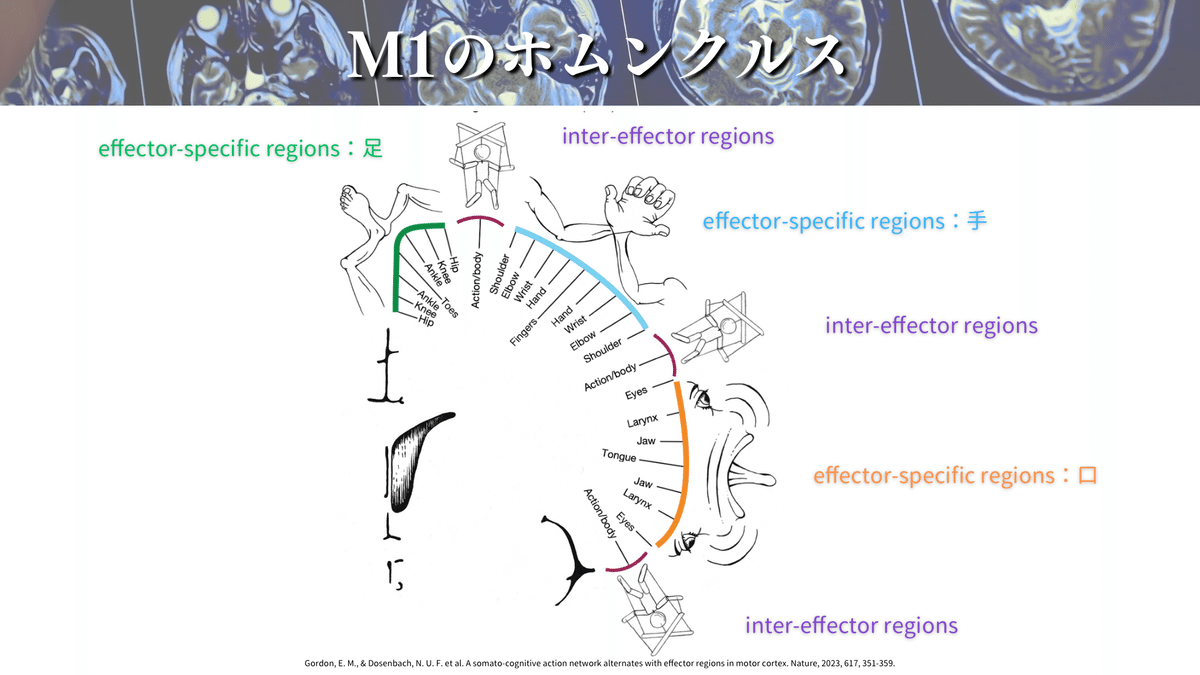

M1にはホムンクルスと呼ばれる身体機能局在があります(下図)!

簡単にいうと手を動かすことに特化した領域や、足を動かすことに特化した領域があるということです🖐️🦶(ちなみにこれを効果器特異的領域と言います)

この図のように下肢🦶は内側にあり、上肢は真ん中あたりでhandknobの周辺にありますね!

これに関しては上図を見るとイメージできるかと思いますが、口顔の効果器特異的領域は左の画像の「5」に相当していて、耳よりに位置しています。

このレベルでは口顔👄の効果器特異的領域も見えてくるかもしれません!

これによると、最も前外側に位置するのが口顔の線維であり、最も後内方に位置するのが下肢の線維ということが一目でわかりますね😳

これまでの参考書などを参考にすると上肢→体幹→下肢の順番に並んでいそうですが、新しいホムンクルスを参考にすると上肢と下肢の前後にも存在していそうですよね🤔(めっちゃ私見です)